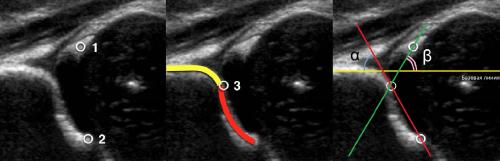

На первом этапе тазобедренный сустав сканируют в продольной плоскости. Проводят основные линии, измеряют костное покрытие головки, расстояние от лобковой кости до головки, ∠α и ∠β, а также определяют тип строения по Графу.

Датчик располагают в проекции большого вертела параллельно поясничному отделу позвоночника. Найдите самое глубокое место вертлужной впадины. Отрегулируйте наклон датчика, чтобы линия тела подвздошной кости лежала строго горизонтально (2).

Пока головка бедренной кости хрящевой плотности, имеется акустическое окно для исследования вертлужной впадины. При продольном сканировании документируют по два снимка: первый — обзорный, второй — с линиями и углами.

Линии костной (красная) и хрящевой (зеленая) крыши проходят через костный выступ, а так же начало Y-хряща и центр гиперэхогенного кончика суставной губы, соответственно. Степень развития костной крыши определяет ∠α, а хрящевой крыши ∠β.

Если край подвздошной кости округлый, костный выступ определяют в точке перехода дуги наружного контура вертлужной впадины в дугу наружного контура подвздошной кости. Обратите внимание, все линии проходят по наружному контуру костей.